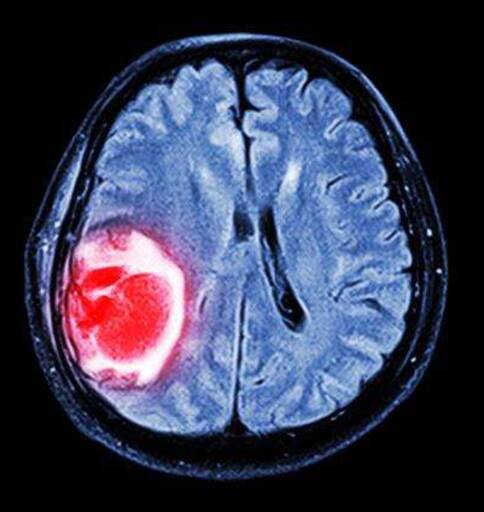

脑瘤是常见的恶性肿瘤,在脑瘤中胶质细胞瘤,占到45%,居脑瘤之首(其中胶质母细胞瘤约占胶质瘤的40%,胶母恶性度较高),脑瘤在切除后,癌细胞还是会生长的,这让人很头疼,美国加州大学旧金山分校(UCSF)的研究人员发现了位于TERT基因启动子上的基因突变如何赋予肿瘤细胞“长生不老”特性的秘密。这一发现可能提供治疗癌症的新方法。